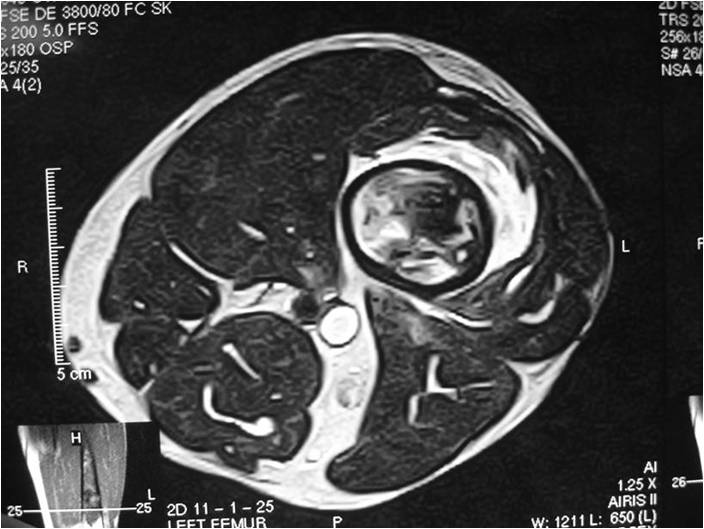

Radiology emulates pathology: Biphasic Tumor

- One region low grade chondrosarcoma

- Second more aggressive area with bone destruction, lysis of calcification, soft tissue mass

- Cortical permeation and a soft tissue mass in 70% of cases

Characteristically abrupt transition between chondroid tumor and dedifferentiated, lytic component